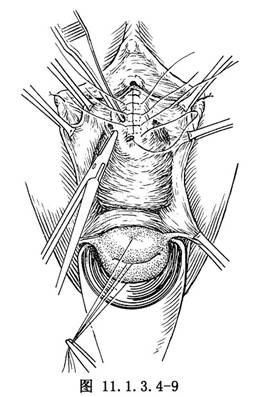

(3)尿道膨出顯著者,於尿道兩旁組織,可加固一層褥狀縫合(圖11.1.3.4-9)。